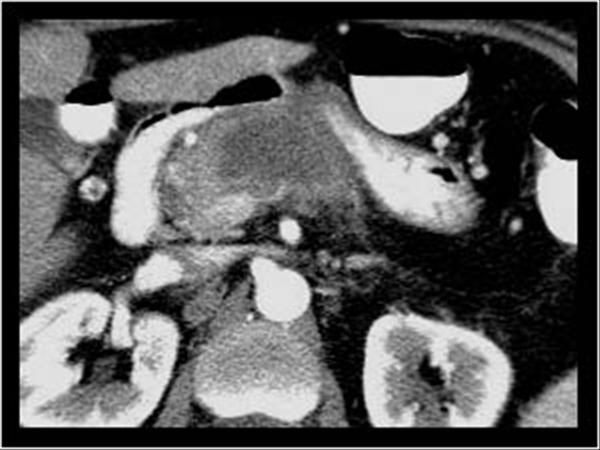

U tụy

» Thông tin: Nữ giới – 57 tuổi.

» Lâm sàng: Sút cân.